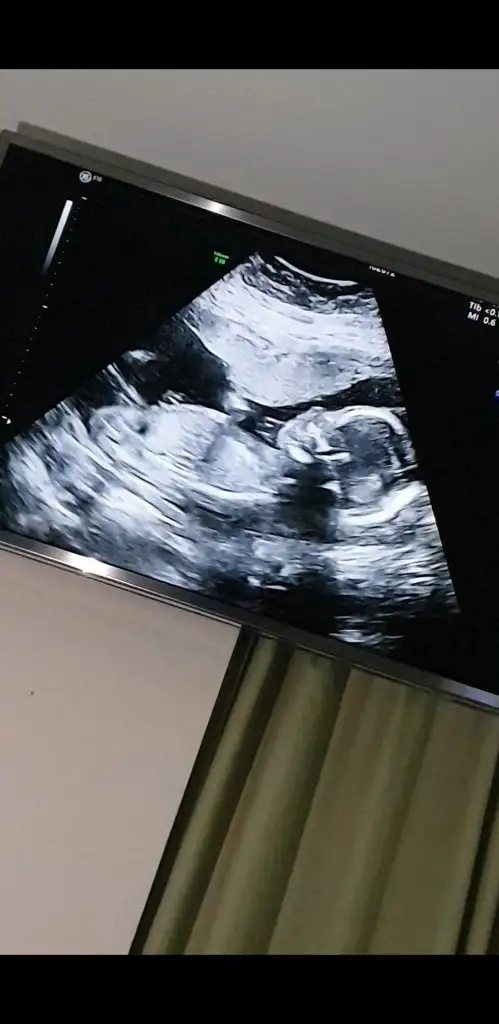

Ikra hanım merhaba 11+1den karından usg atıyorum rica etsem tahminde bulunur musunuz arkadaşım için bana kız demiştiniz doğru cıktı 🤭😊

Anketimi oylarsaniz sevinirim sağlıkla gelsin prenses 🥰

Merhaba nolur benim için de yorumda bulunun mümkün ise🙏🏻 Ikra meyra Ikra meyra şimdiden çok tşk ederim🌻